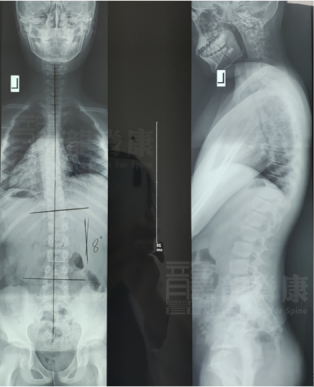

深圳龍脊康醫(yī)師部黃耿沛主任,在不久前,就接診了類似的案例,讓我們一起來看看他的分享:10歲男孩在半年前被發(fā)現(xiàn)高低肩、體態(tài)異常,于是家長趕緊帶孩子到醫(yī)院拍片,確診脊柱側(cè)彎Cobb角約8°,生理曲度除了頸曲反弓的趨勢外,胸腰椎的曲度存在。

所以,黃耿沛主任給孩子定制了運(yùn)動康復(fù)訓(xùn)練的治療。通過一次的訓(xùn)練后,從下圖中我們可以看出:訓(xùn)練前男生右肩高,左臀高,身體左后旋;訓(xùn)練后體態(tài)恢復(fù)正常。